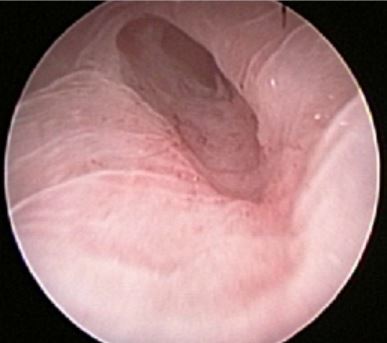

Endometrial injury is a simple, low-cost procedure which can be performed on an outpatient basis.